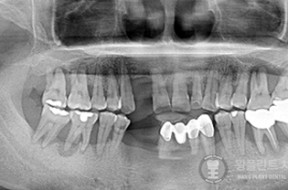

전후사례